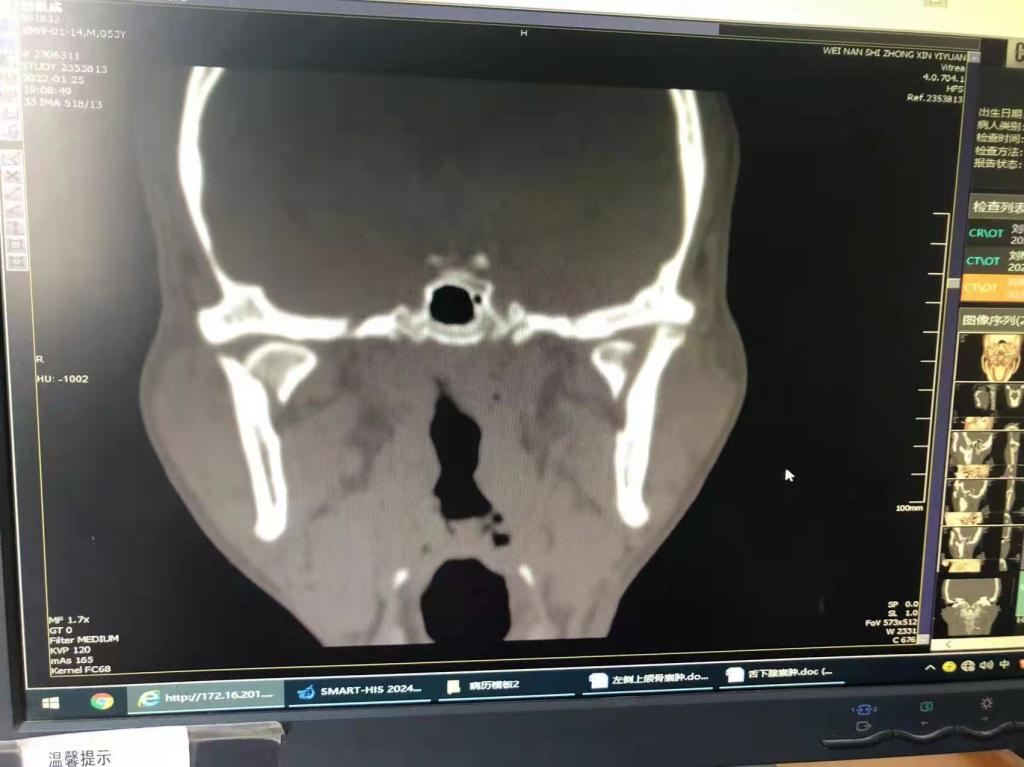

据了解,53岁的患者刘先生在1月25日当天走路不慎摔倒致下颌损伤,造成颏部软组织裂伤和张口困难,前往当地卫生院进行颏部裂伤清创缝合术。术后辗转到乐鱼手机站入口口腔科门诊就诊,并进行颌面部CT检查提示为下颌颏部正中和双侧髁状突骨折,双侧下颌升支高度不一致,右侧较左侧变短1cm,张口重度困难,咬合关系错乱。刘先生因考虑在春节过后再入院治疗,于2月8日再次前来口腔科以“下颌骨骨折”收治人院。

口腔科主治医师蔺非非为患者入院后进行完善术前常规检查和颌间牵引恢复咬合关系。科主任李瑞春结合患者实际病情和检查结果认为,患者的髁突骨折在下颌骨骨折中所占比例较高,约为17.0%-36.3%。髁突骨折时,耳前区有明显的疼痛,局部肿胀、压痛。通过手指深入外耳道或在髁突部触诊,如张口时髁突运动消失,可能有骨折段移位。双侧低位骨折时,2个髁突均被翼外肌拉向前内方,双侧下颌支被拉向上方,可出现后牙早接触,前牙开秴。髁状突骨折易引起下颌后缩,张口困难,咬合关系错乱,关节强直等并发症。考虑患者系陈旧性骨折应尽早实施手术,避免骨折导致的张口困难、关节强直等并发症。因患者已经错过最佳治疗时期,决定尽快为患者进行手术治疗。

科主任李瑞春和主治医师蔺非非经过缜密的术前讨论和充分评估,手术在全身麻醉下进行,术中克服术野狭小操作不便困难,将下颌骨骨折完好对位,顺利地完成了"双侧髁状突和下颌颏部正中骨折切开复位内固定术"。术后检查患者面部对称,双侧下颌升支高度一致,咬合关系已恢复。